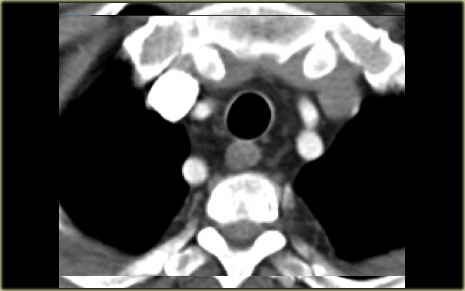

Innominate artery compression syndrome

On the left a sagittal scanogram, axial image and sagittal reconstruction of a 5 year old girl with noisy breathing and occasional episodes of cyanosis.

First look at the images then continue.

The findings are:

- anterior compression of the trachea

- brachiocephalic (innominate) artery is located more to the left and compresses the trachea

The diagnosis is the innominate artery compression syndrome.

In infants the innominate artery arises more to the left than in adults, so it’s got to go in front of the trachea.

It may compress the trachea, leading to stridor, cough and dyspnea.

This compression decreases with age and these patients will outgrow it.

The compression in the innominate artery compression syndrome is located on the right anterior side and at the level of the thoracic inlet.

This is much higher than in the double arch or Right Aortic Arch with Aberrant left subclavian

On the left another case with mild compression on the trachea.